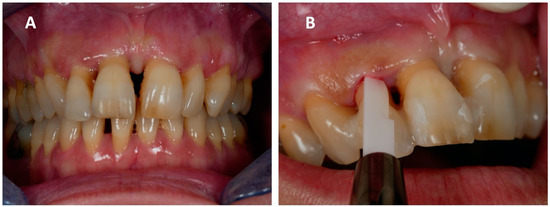

2. Case Report